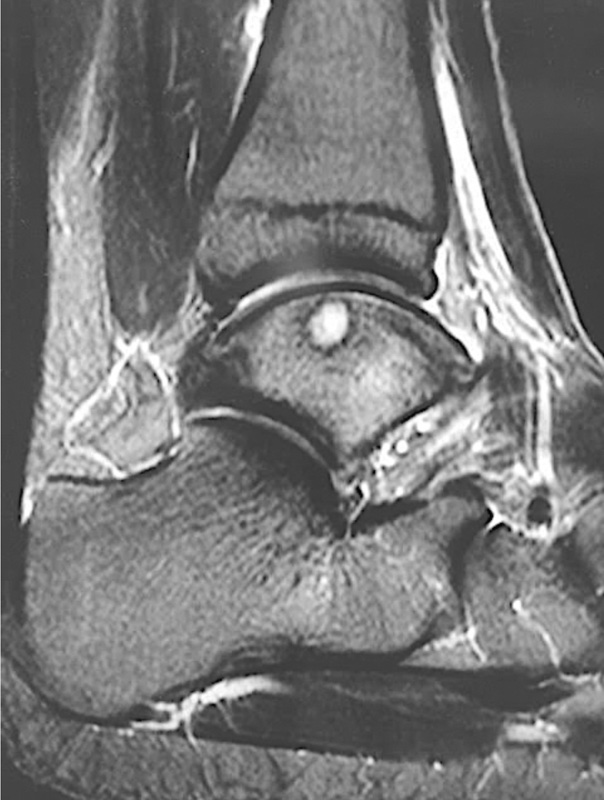

Nelle articolazioni sottoposte a carico durante il processo artrosico, la formazione di cisti subcondrali o geodi, genererà un ulteriore peggioramento a livello dell’unità morfofunzionale osteocondrale (Fig. 1).

Inoltre, il danno alla cartilagine articolare porta al rilascio di mediatori dell’infiammazione, con conseguente aumento del turnover dell’osso subcondrale. Ciò determinerà la formazione di crepe sulla superficie ossea al di sotto della cartilagine, osteofiti e riassorbimento osseo. Il liquido sinoviale penetrerà quindi in queste aree favorendo la formazione di cavità cistiche (Fig. 2). La conseguenza è una riduzione della rima articolare e la sclerosi dell’osso subcondrale4.